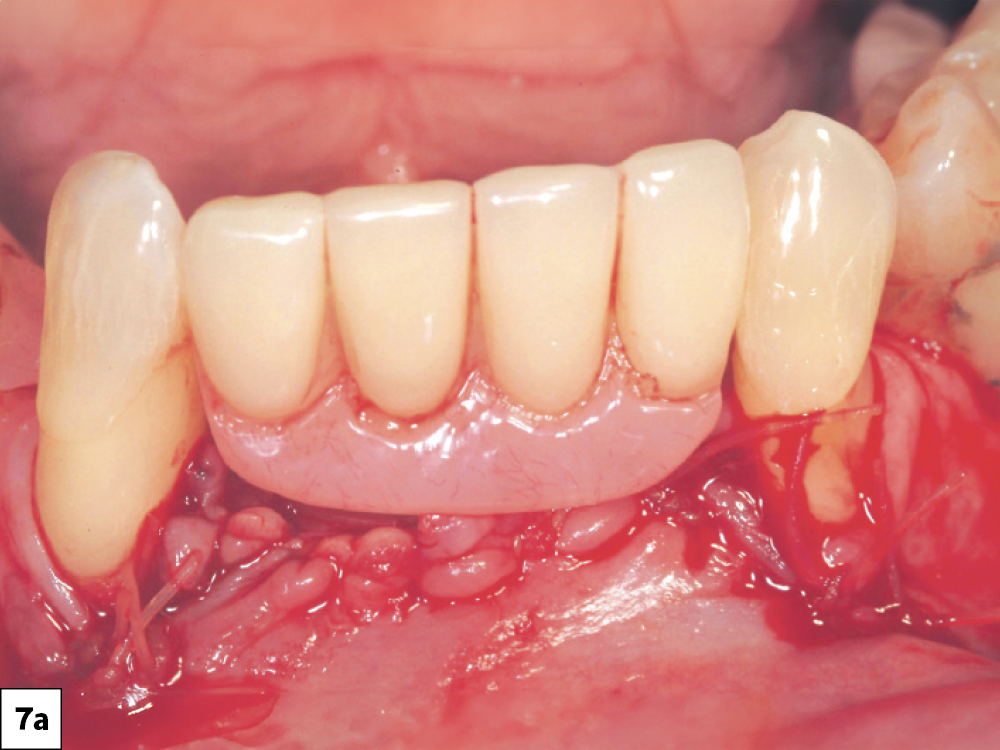

10. No Interim Prosthesis Pressure

If an interim prosthesis places pressure on the surgical wound the microcirculation may be affected, resulting in compromised blood supply to the wound edges.6 The clinician should modify interim prostheses to avoid force being directed on the surgical site and instruct the patient to avoid direct mastication on the surgical site area (Figs. 7a, 7b).

Interim Prosthesis Pressure: (a) The prosthesis should be evaluated for direct pressure on the surgical site, (b) removal of any areas of tissue impingement.

Figures 7a, 7b: Interim Prosthesis Pressure: (a) The prosthesis should be evaluated for direct pressure on the surgical site, (b) removal of any areas of tissue impingement.